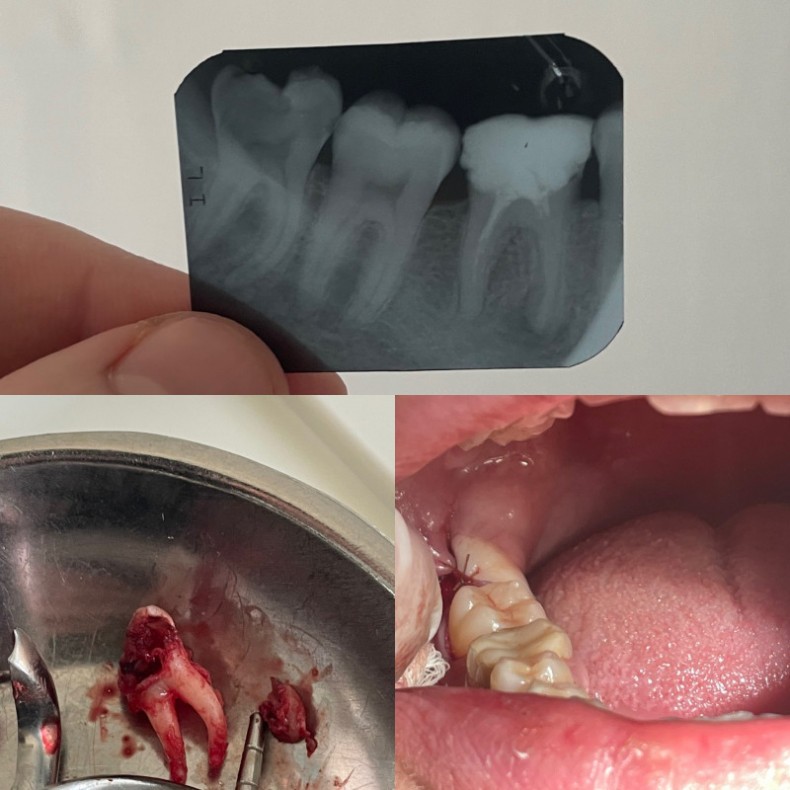

Видалення зубів, видаленн коренів зубів

Видалення 8 зубів різних рівнів складності.

Видалення зруйнованих зубів.

Атравматично видаляємо зуби, для запобігання ускладнень. У вартість послуги входить знеболення(анастезія), гемостатична губка та ушивання рани після видалення.

Також проводимо контроль загоєння після видалення.